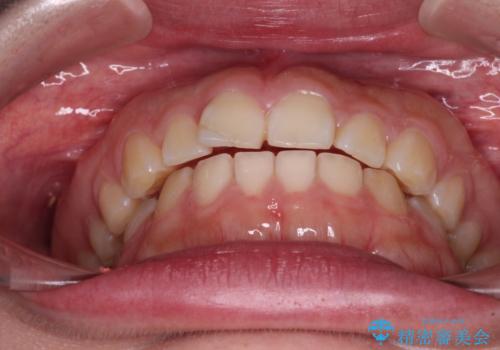

- 出っ歯と口の閉じにくさ、デコボコを気にして来院された患者様です。

口元の突出感を改善するため、上下左右第一小臼歯4本の抜歯を行い、ワイヤー装置による矯正治療を行うこととしました。

抜歯矯正を行ったことで、顎先のつっぱり感や口元の閉じにくさを解消することができました。